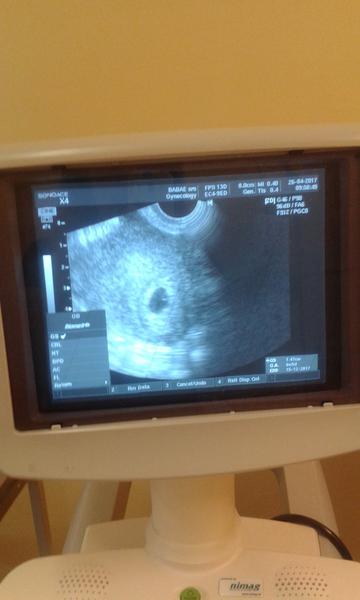

krv mi nebral este ze to az teraz ked dojdem..a srdiecko este nebilo ale babetko uz tam bolo lebo bolo vidiet v tom vaku malu bodecku ...🙂

@kotatko12345 to este len teraz bude mat babo 20mm v tom tyzdni bolo vidiet len bodku ako si vravela to mohlo mat od 5 mm do 13mm ja som bola 6plus4 /7 tyzden lekar mi povedal ze uz je tam akcia srdiecka a plod mam 7.7mm tebe to tak lekar nevysvetlil nezmeral si to ?

@archanjel007 no prvy krat co som tam bola povedal mi ze mam sliznicu moc vysoko ...druhy krat co som bola robil zase sono a potvrdil ze som tehu a spravila som si foto.a teraz idem 3x

@olylili tak to som zvedava ako podrastlo babo od 26.4